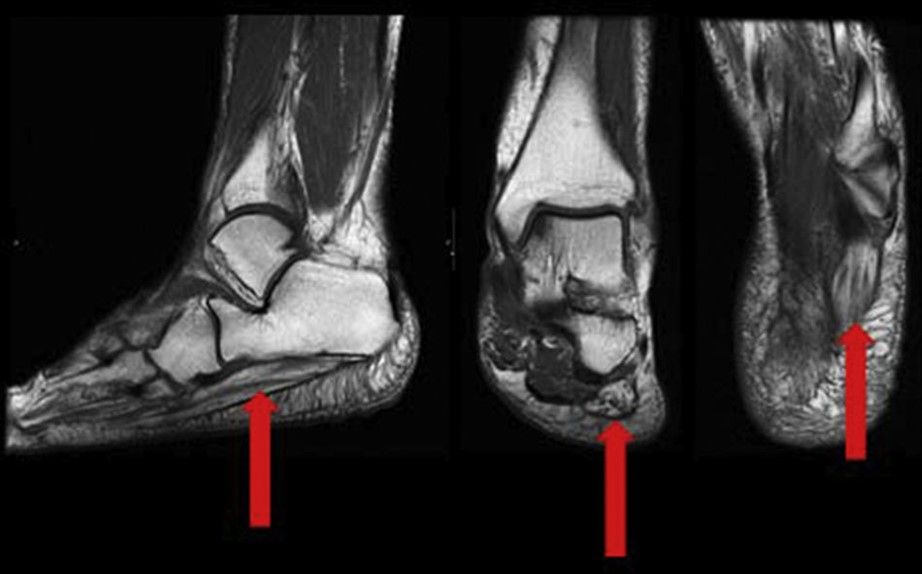

- Resonancia magnética (RM): puede mostrar cambios en el músculo abductor del quinto dedo por denervación (atrofia, edema).